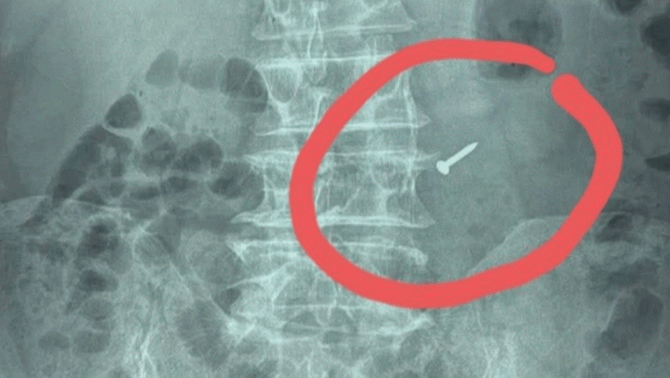

Ngay khi phát hiện người đàn ông nuốt phải chiếc đinh nhọn xuống dạ dày, gia đình đã lập tức đưa ông đến bệnh viện.